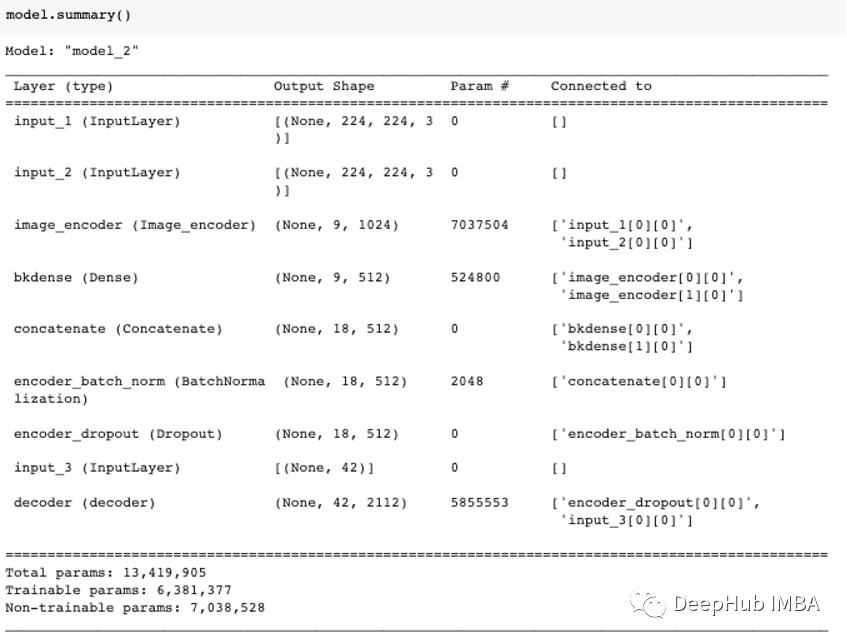

我们的模型结构如下:

训练的参数如下:

batch_size = 100

embedding_dim = 300

dense_dim = 512

lstm_units = dense_dim

dropout_rate = 0.2

lr (Learning Rate) = 10**-2

number of epochs = 10

min_lr (Minimum Learning rate) =10**-7